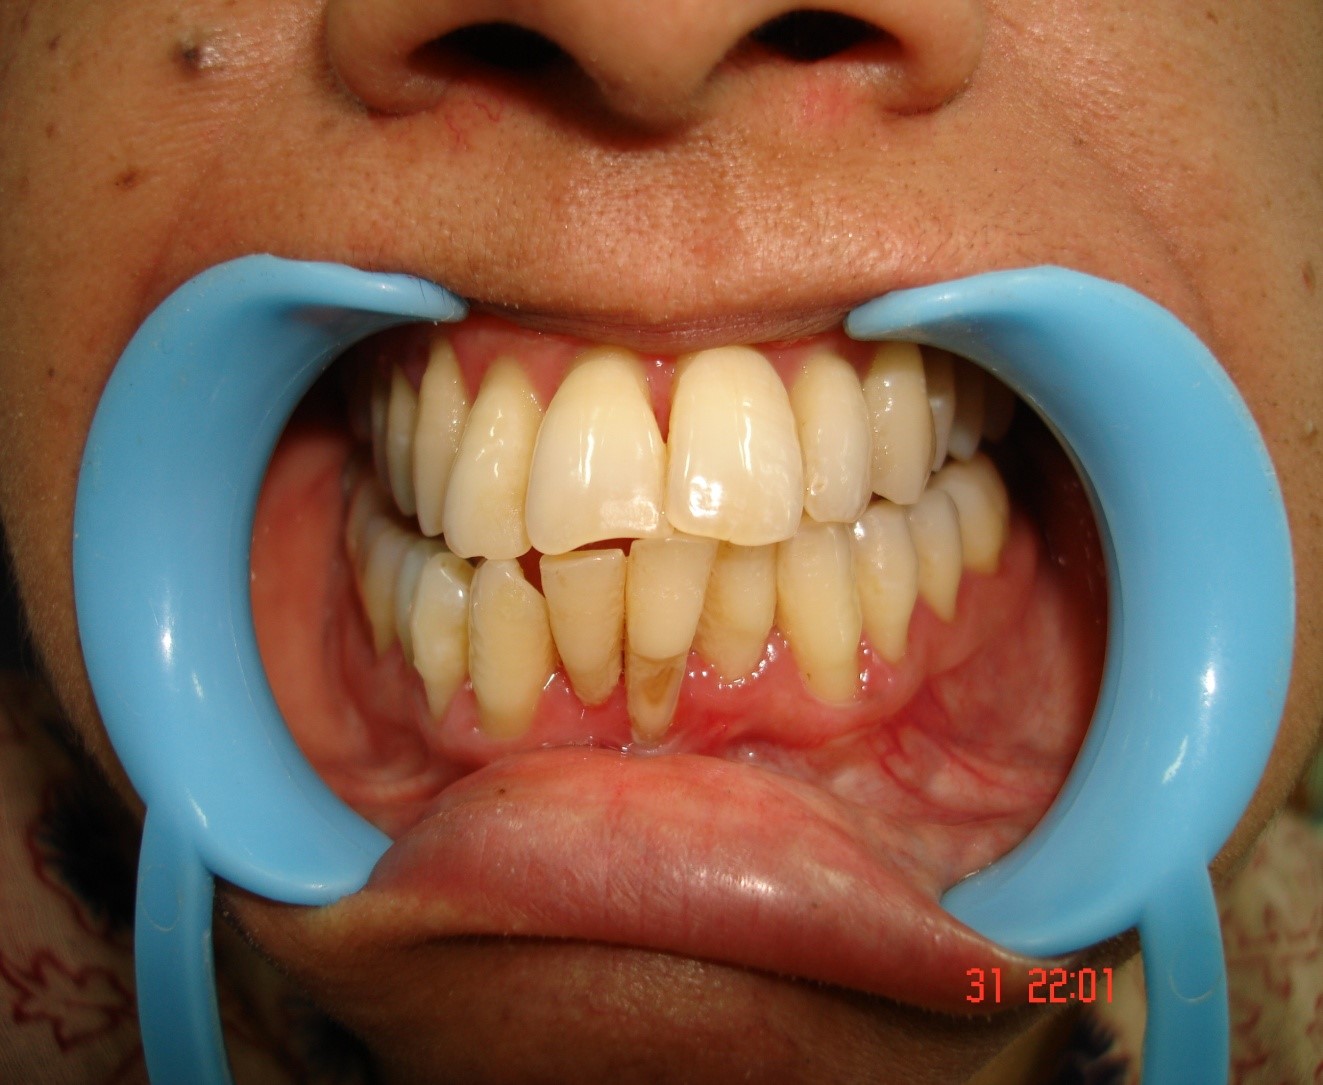

Pyorrhoea is any kind of gum disease in which the ligaments and bone that supports the teeth become inflamed and infected. Bone loss from pyorrhoea is the primary cause of tooth loss in adults. The onset is marked by bleeding of the gums, pus discharge, loosening of teeth. The main aim of the treatment is to control the infection and if possible stop it. The first step is to implement a good oral hygiene program, professional teeth cleaning from your dentist every 6 months. Your dentist may even recommend deep cleaning, gum survey or bone graft depending upon the condition of the teeth and gums.